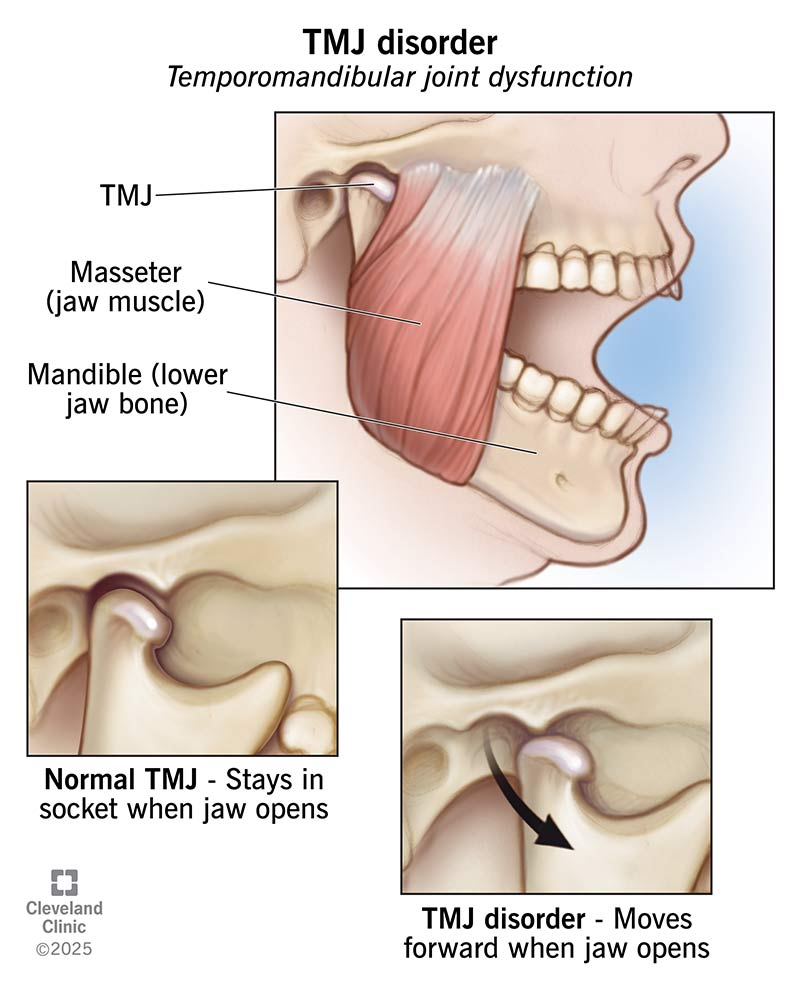

TMJ AND MUSCLE TENSION RELIEF

We can name two types of tension or pain:

Related to TMJ (your jaw joints)

If the problem originates from the joint and it is addressed by replacing/correcting it, TMJ issues usually will disappear completely.

Muscle-related tension

This usually results from improper jaw positioning or tongue posture.

When the jaw is moved forward (maxilla adjustment), the tongue gains more space, adopts a natural position, and muscle tension is typically relieved.

Segmental lefort expansion can also help the tongue reposition correctly, further reducing tension.